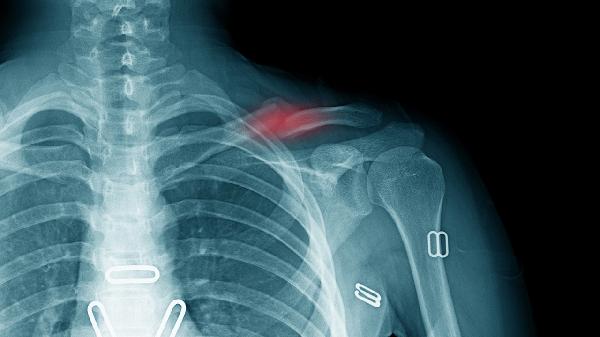

锁骨骨折后除钙剂补充外,需保证每日500毫升乳制品摄入,多食用豆腐、芝麻酱等富钙食物。适度晒太阳促进皮肤合成维生素D,康复期进行肩关节被动活动防止僵硬。避免吸烟饮酒影响骨愈合,定期复查X线观察骨痂形成情况。睡眠时保持患侧上肢垫高减轻肿胀,营养均衡摄入蛋白质和胶原蛋白前体物质。